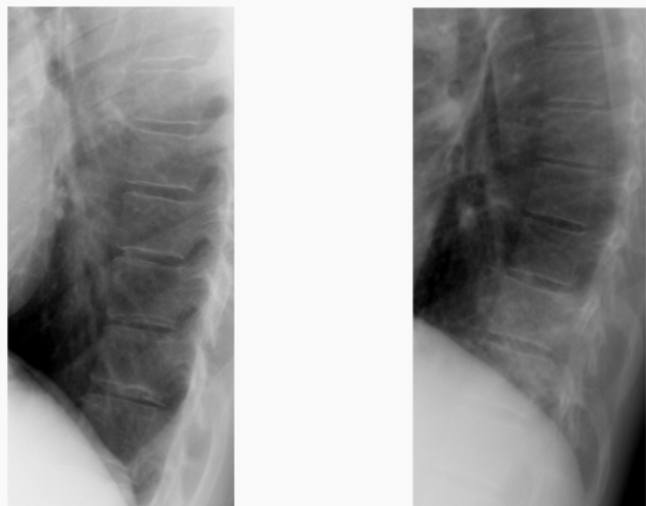

Patterns of atelectasis are very similar to consolidation except:

Volume loss

Left upper lobe collapse